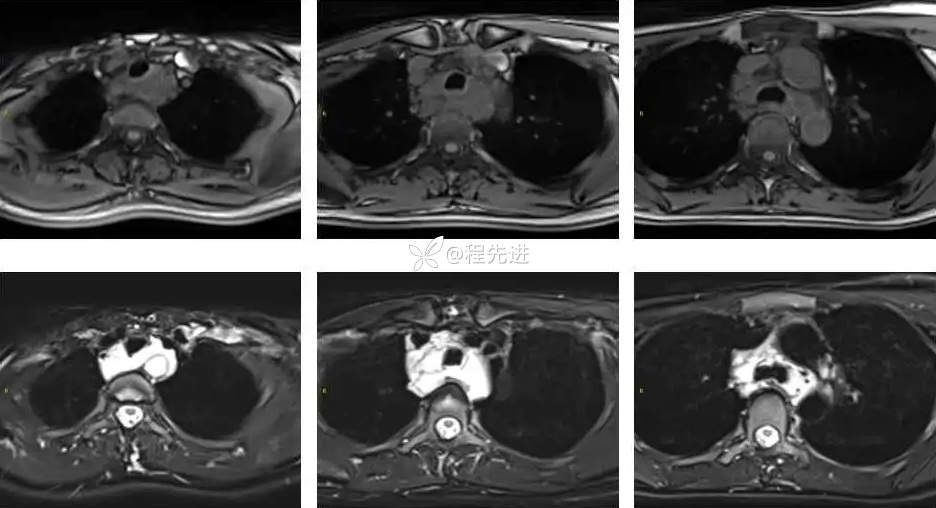

MRI平扫+增强:

T1、T1增强: